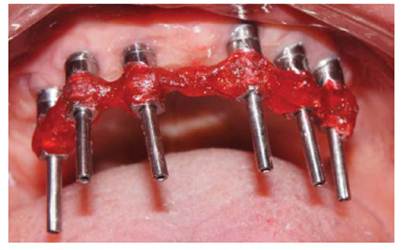

Se procedió a la transferencia de los pilares en el maxilar superior con cubeta abierta y ferulización de transfer (Figura 4), y a la transferencia de la plataforma de los implantes en el maxilar inferior.

Luego se procedió a la fabricación de la estructura metálica del maxilar superior con la ayuda de una pantalla de silicona obtenida del protocolo reverso, esta estructura presentó un asentamiento pasivo comprobado clínica y radiográficamente luego de realizar los cortes y soldajes necesarios (Figura 5). Se realizó el enfilado para la prótesis híbrida con dientes Ivostar/Gnathostar donde se evaluó estética y fonación. En el maxilar inferior se torquearon los pilares CM recto para la pieza 35 y Pilares angulados (17°) a nivel de piezas 36 y 46 fresados con la ayuda de una guía de colocación de pilares (Figura 6) y se fabricaron coronas de metal cerámica. Para finalizar se procede a la instalación de la prótesis híbrida superior, la cementación de las coronas con cemento temporal y la instalación de una férula de DCM (figura a y b). Finalizado el tratamiento se realizaron controles periodontales y protésicos periódicos donde se comprobó la correcta concientización del paciente en cuanto a su mantenimiento. (Figura 8)